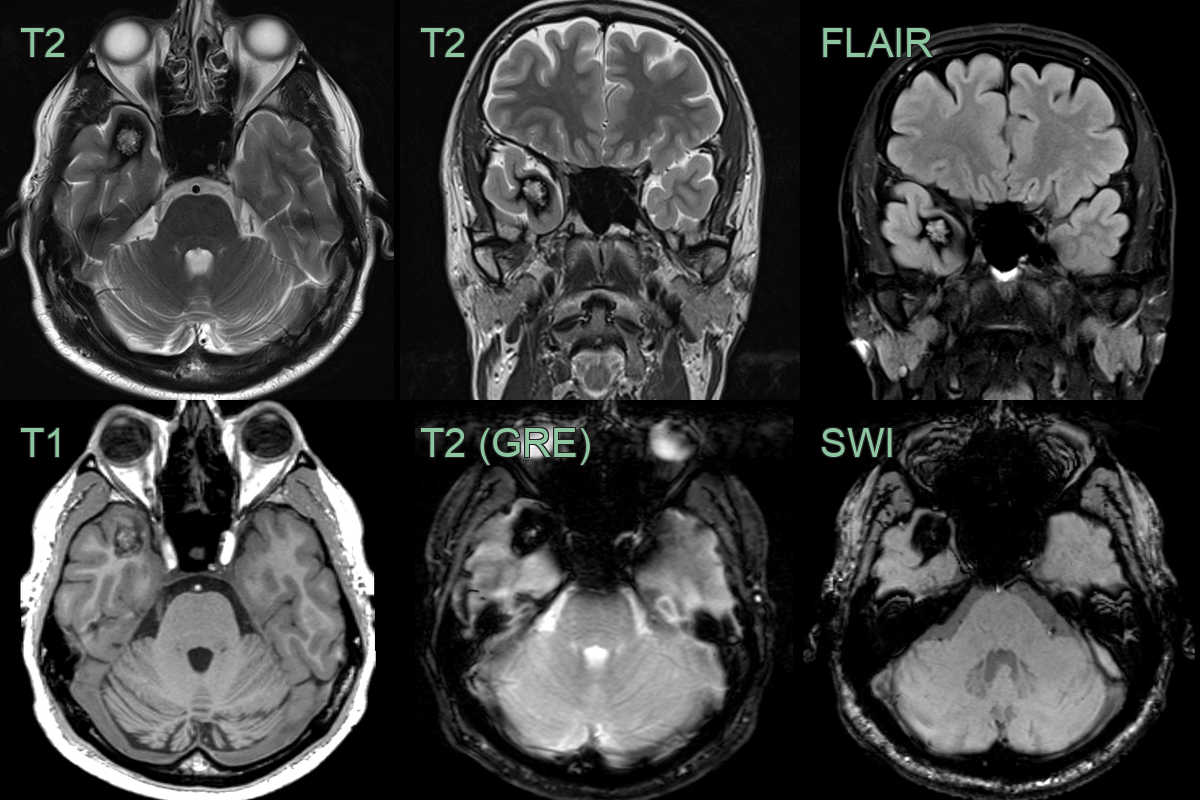

- A 30-year-old presented with left-sided facial weakness and numbness.

- The initial MRI showed a T1- and T2-hyperintense lesion in the left side of the pontine tegmentum, consistent with a recent hemorrhage within a cavernoma. SWI showed a network of small vessels representing an associated development venous anomaly

- 6 months later, mild rim of edema on FLAIR, blooming artefact and T1-hyperintensity had regressed.